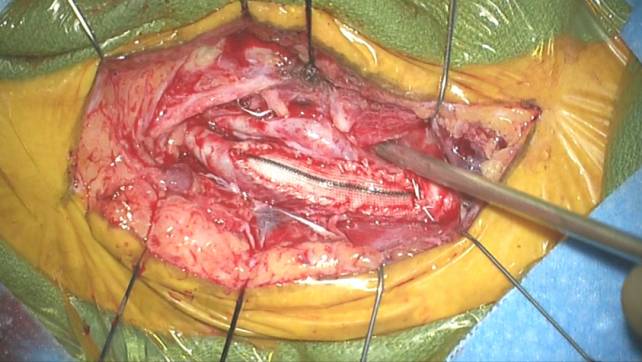

补片血管成形术

应该避免在血管切开处常规使用补片。当颈内动脉管径小,并且动脉切开的边缘不整齐时笔者选择性使用Hemashield补片。缝合补片的原则和上面提及的血管缝合原则相似。附件中的录像将进一步说明补片技术。

把补片放置在动脉切开上方来修剪补片至合适的长度。补片两端再修剪成细窄状。笔者采用双针6-0普瑞林将补片的ICA端和动脉切开的远端缝合在一起,同时用橡皮脚垫的钳夹固定缝线在位。用连续不打结缝合方式缝合从ICA到CCA的内侧壁,然后继续缝合至外侧壁的中间。接下来,用双针缝线的另一针缝合剩下的未吻合的外侧壁。

下面的术中照片用来举例说明右侧经内动脉内膜剥脱术的手术步骤:

图21h. 在颈总动脉内血管切开的近端,斑块横断后的瓣膜缝合到外壁上。

图21i. 同样,颈内动脉内动脉切开的远端内膜瓣也应被缝合。

图21j. 在内侧吻合线中点二根缝线会师。

图21k. 展示补片成形后的最后效果。